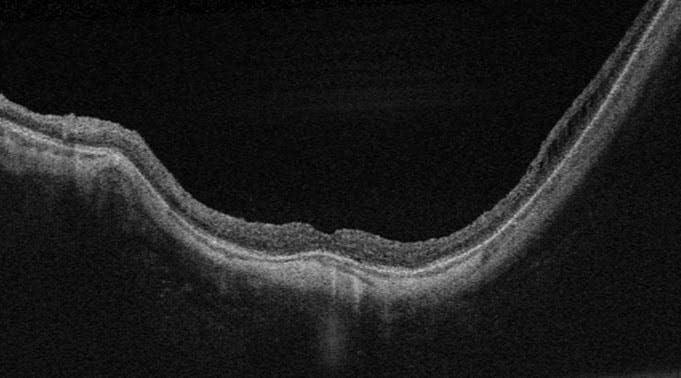

One month post-surgery, the left eye’s VA had improved to 20/40, and the follow-up OCT showed complete resolution of the macular schisis and recovery of the foveal contour (Figure 3). Overall, the patient's symptoms had significantly improved, and he continued with routine follow-up as scheduled.

<p>Figure 3. OCT after 1 month of follow-up shows decreased retinal thickness, significant improvement in the retinal schisis, no ERM, and complete resolution of the neurosensory detachment.</p>

Figure 3. OCT after 1 month of follow-up shows decreased retinal thickness, significant improvement in the retinal schisis, no ERM, and complete resolution of the neurosensory detachment.